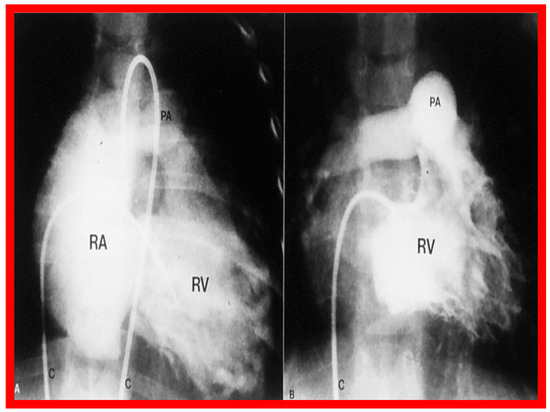

3.1. Pulmonary Stenosis

Pulmonary Stenosis in the Fetus